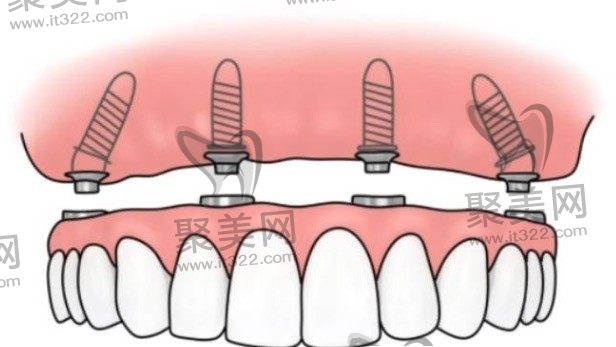

半口牙种植指的是一种以植入骨组织内的下部结构为基础来支持、固位上部牙修复体的缺牙修复方式。它包括下部的支持种植体和上部的牙修复体两部分。它采用人工材料(如金属、陶瓷等)制成种植体(一般类似牙根形态),经手术方法植入组织内(通常是上下颌)并获得骨组织牢固的固位支持,通过特殊的装置和方式连接支持上部的牙修复体。

半口种植牙的全过程,包括位置的选定,粘膜切开,备洞钻孔,种植体植入,最后的粘膜缝合的过程。在进行种植牙治疗时,位置的选择非常关键,需要选择在骨质较好的位置,进行粘膜切开后选择骨质条件好的位置进行种植窝洞的制备,按照骨头的宽度,高度及长度选择合适直径的种植体进行植入,最后进行粘膜的缝合。全口或半口种植牙后,在保证一定的骨结合和初期稳定性后,可以选择即可修复来恢复牙齿的咀嚼。